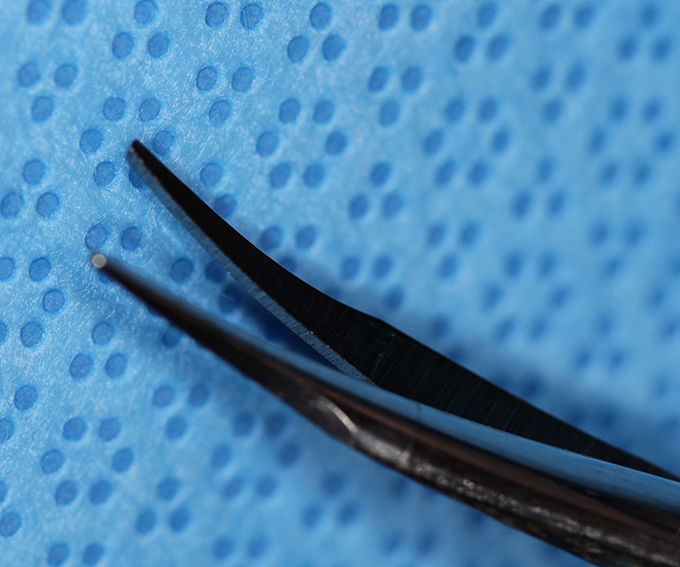

Forcep Thumb, McPherson tying iris straight

(aka straight tie forceps)

catalog number: Storz E1815S

Typical Use(s): Tying suture, placing and removing iris hooks

Forcep Thumb, McPherson tying iris straight (Enlarged)

(aka straight tie forceps)

catalog number: Storz E1815S

Typical Use(s): Tying suture, placing and removing iris hooks

Forcep Thumb, McPherson tying iris angled

(aka straight tie forceps)

catalog number: Storz E1815A

Typical Use(s): Tying suture

Forcep Thumb, McPherson tying iris angled (Enlarged)

(aka straight tie forceps)

catalog number: Storz E1815A

Typical Use(s): Tying suture